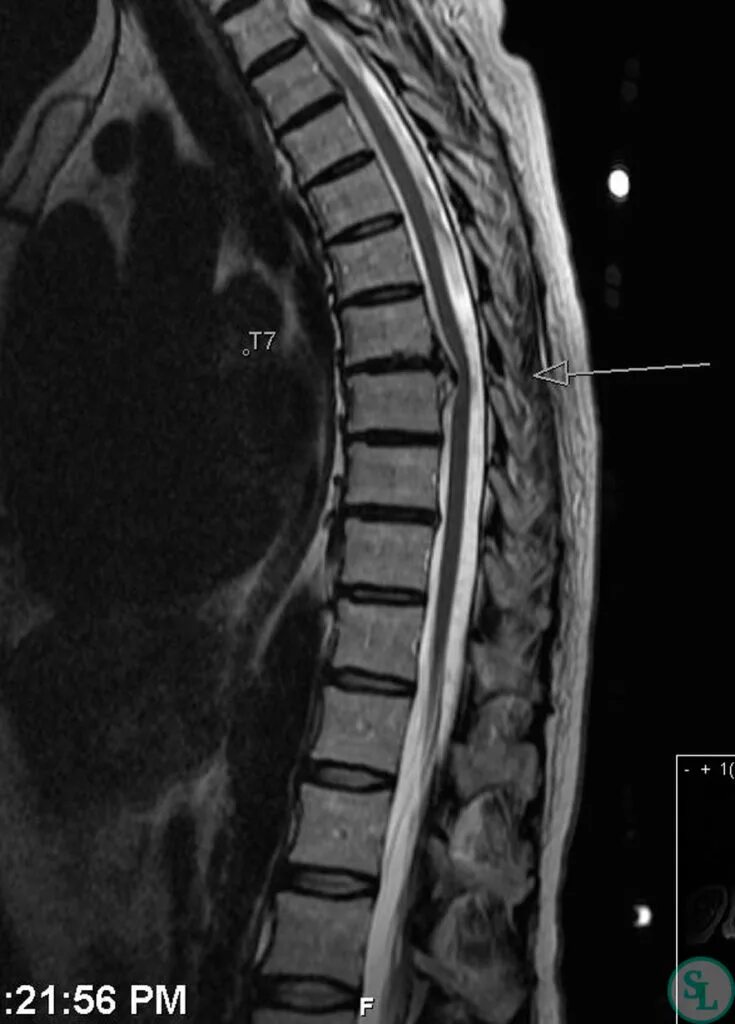

Как лечить грудную грыжу позвоночника